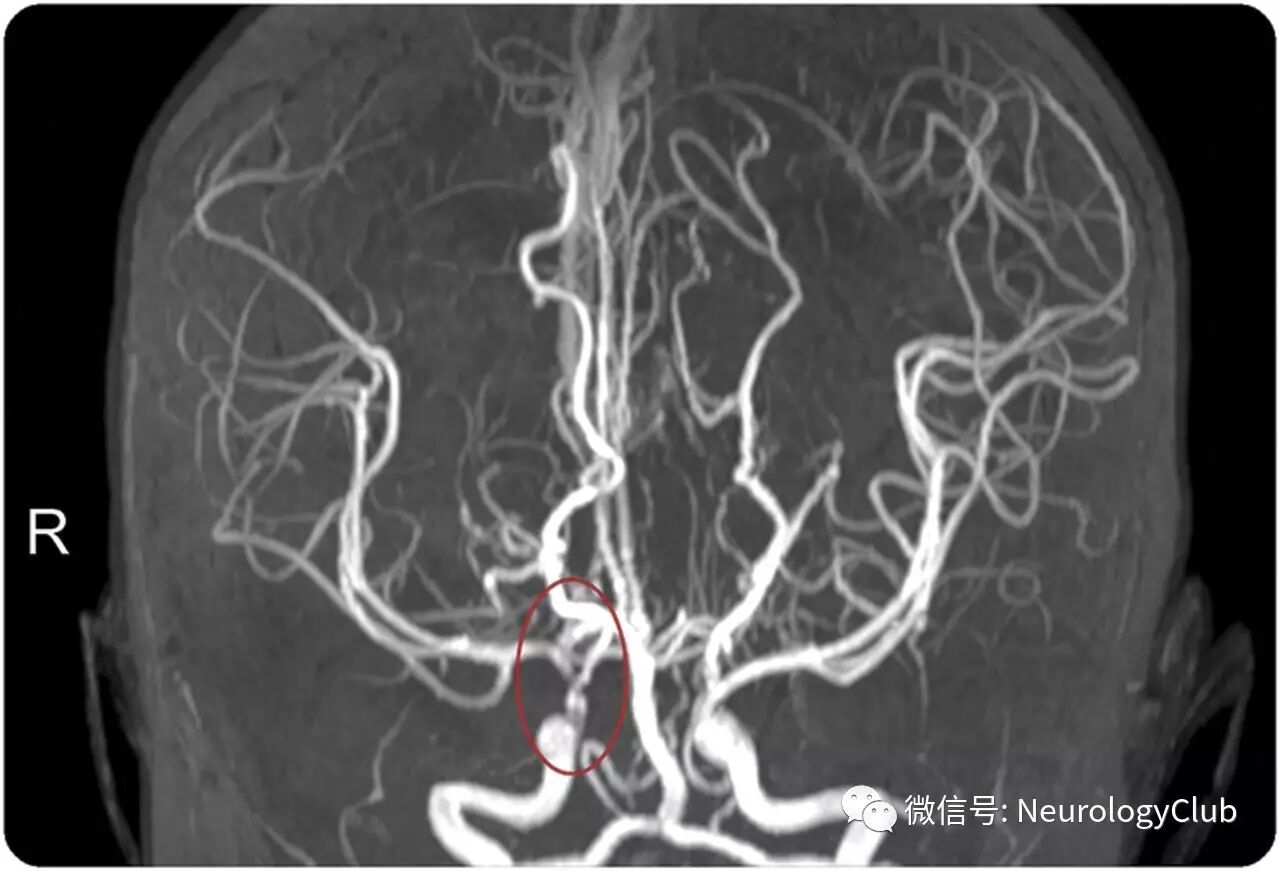

(图2:MRI血管造影:右侧颈内动脉末端明显狭窄)